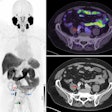

PET/MRI imaging may be a valuable option over PET/CT for planning surgery in women with endometrial cancer, according to a study published September 1 in BMC Cancer.

A Chinese team in Shenyang compared how well the methods performed at identifying the severity of tumors prior to surgery in a group of patients with endometrial cancer. PET/MRI was more accurate than PET/CT at classifying early tumors, as well as visualizing cancer invasion in surrounding tissue, the group found.

Hybrid PET/MRI imaging is a relatively new approach that combines the anatomical and functional advantages of both techniques in a single scanner. In this study, the authors explored the value of PET/MRI for the first time in endometrial carcinoma staging and compared it to PET/CT.

The overall accuracy of FIGO staging was 86% (49/57) for PET/MRI and 77.2% (44/47) for PET/CT, according to the findings. PET/MRI overstaged the actual FIGO stage in five patients, whereas PET/CT overstaged the actual FIGO stage in nine patients.

FIGO stage II pathologically confirmed moderately differentiated adenocarcinoma in a 57-year-old female patient. (A) Axial PET/MR images. (B) Axial MR T2-weighted images. (C) Axial PET/CT images. (D) Axial CT images. (E) Sagittal PET/MR images. (F) Sagittal PET/CT images. PET/MRI and MRI show the endometrial carcinoma invading the cervical stroma. PET/CT also shows the endometrial carcinoma invading the cervical stroma, yet the extension of the tumor is difficult to determine. The PET/MRI and PET/CT staging were consistent with the pathological stage, namely FIGO stage II. The white arrow indicates endometrial carcinoma. Image courtesy of BMC Cancer.

FIGO stage II pathologically confirmed moderately differentiated adenocarcinoma in a 57-year-old female patient. (A) Axial PET/MR images. (B) Axial MR T2-weighted images. (C) Axial PET/CT images. (D) Axial CT images. (E) Sagittal PET/MR images. (F) Sagittal PET/CT images. PET/MRI and MRI show the endometrial carcinoma invading the cervical stroma. PET/CT also shows the endometrial carcinoma invading the cervical stroma, yet the extension of the tumor is difficult to determine. The PET/MRI and PET/CT staging were consistent with the pathological stage, namely FIGO stage II. The white arrow indicates endometrial carcinoma. Image courtesy of BMC Cancer.In addition, an analysis of quantitative measures based on F-18 FDG PET/MRI radiotracer uptake by the tumors and nearby tissue were significantly different between stage I and stage III tumors, the authors wrote.

"PET/MRI had higher accuracy for endometrial carcinoma staging, mainly for FIGO stage I tumors. This was mainly owing to PET/MRI having higher diagnostic accuracy for detecting the depth of myometrial invasion," they wrote.